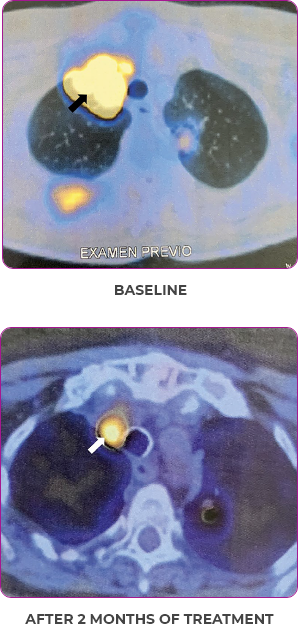

Reduction in tumor burden1

MRIa imagery of the brain. Red line indicates the maximum dimension.1

aMRI, magnetic resonance imaging.

Pre- and post-treatment imaging, by DuBois SG et al, is licensed under CC BY 4.0.

Response to VITRAKVI1

- Patient achieved a confirmed partial response after 4 cycles of VITRAKVI with a 45% reduction in tumor burden

- Following 6 cycles of VITRAKVI, the patient was referred for definitive limb-sparing surgery

- Pathology revealed a complete pathologic response and clear resection margins with scar tissue noted